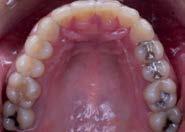

En los estudios intraorales de inicio en las fotografías se muestra en la de frente el diastema anterior, con la línea media dental superior e inferior no coincidentes, la mordida profun da anterior (Figura 2), en la lateral derecha clase l molar y canina bila teral (Figura 3), el apiñamiento leve superior e inferior y la forma de las arcadas.

Estudios radiográficos iniciales

En la radiografía lateral de cráneo se ve el diagnósitico: clase II esqueléti ca, con crecimiento hiperdivergente, mordida profunda anterior (Figura 4).

En la radiografía panorámica se observa 28 piezas dentales, con un diastema en los incisivos centrales (Figura 5).